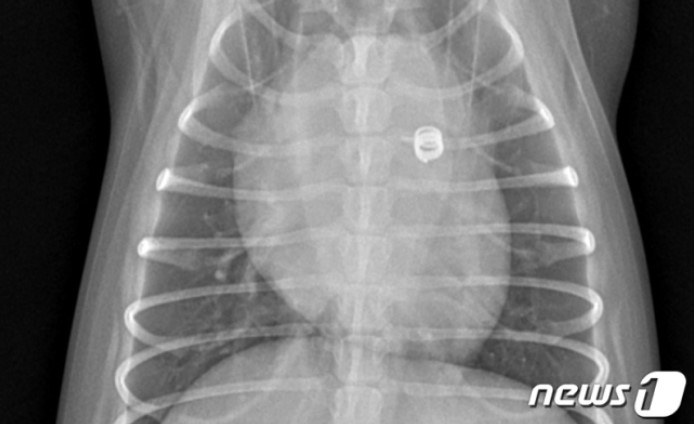

"침대 조심하세요"…강아지 낙상 후 골절된 앞다리 치료법은[VIP벳]

"침대 조심하세요"…강아지 낙상 후 골절된 앞다리 치료법은 [VIP벳]VIP동물의료센터 청담점 치료 사례강아지 상완골 관절 융기 골절 재건술은말티푸 종의 강아지 철이(가명, 1년 10개월)는 침대에서 떨어진 이후 오른쪽 앞다리를 딛지 못하고 아파하는 증상을 보였다. 동물병원에서 방사선 검사상 오른쪽 주관절(사람으로 치면 팔꿈치, 해부학명 shoulder elbow)의 골절과 탈구가 확인됐다. 철이는 곧바로 수술받았고 현재는 회복해 건강하게 지내고 있다.VIP동물의료센터에 따르면 강아지 주관절 골절은 침대나 소파에서 떨어지거나 큰 충격을 받았을 때 주로 발생한다. 골절 이후 강아지는 통증으로 인해 걷지 못하게 되고 고통도 호소한다.[낙상으로 인해 오른쪽 앞다리 골절상을 입은 강아지의 엑스레이 사진]강아지 주관절 골절 치료의 경우 골절편을 정상 해부학적 구조로 맞춘 후 다양한 재료를 사용해 고정할 수 있다. 나사를 사용하거나 핀을 사용할 수 있는데 환자(환견) 뼈의 크기 및 상태, 주변 근육이나 연부 조직의 상태, 개체별 성향, 기저질환 및 여러 요소를 고려해 적절한 재료를 선택해야 한다.치료를 위한 이식물을 삽입하는데 있어 고정과 안착이 잘 돼야 한다. 주변 조직에도 자극이 되지 않아야 하므로 수술 전 철저한 수술 계획을 세우는 것이 중요하다.철이도 이 같은 사항을 고려해 계획하에 수술을 진행했다.철이의 환부 주변 근육을 충분히 이완시키고 뼈를 원위치에 맞춰 수제로 고정한 후 스크류와 핀을 삽입했다. 골절로 인해 생길 수 있는 염증을 관리해주기 위해 멸균생리식염수로 수술 부위를 충분히 세척하는 과정도 거쳤다.[강아지의 앞다리 수술 후 촬영한 엑스레이 사진(VIP동물의료센터 제공)] 수술 후 검사를 통해 골절된 뼈가 잘 교정된 것을 확인했다. 이식물도 목표한 대로 잘 장착됐다. 이후 대칭적 부중 치료를 위한 짐볼 재활치료와 수술 부위 회복을 위한 냉각치료, 레이저치료를 진행했다. 철이는 2주차부터 정상 보행이 가능해졌다.[김종인 VIP동물의료센터 청담점 원장 ⓒ 뉴스1]김종인 원장은 "강아지 주관절이 골절된 경우 신속하고 정확하게 계획해 수술을 하는 것이 중요하다"며 "철이의 경우 골절 후 시간이 경과된 시기에 수술이 진행돼 주변 조직이 구축되다보니 골절부의 환납이 어려웠다. 하지만 적절히 수술해 주변조직을 최대한 보존하며 성공적으로 수술을 마칠 수 있었다"고 밝혔다.이어 "사람과 마찬가지로 강아지 다리 골절이 발생한 경우 최대한 빠르게 병원에 내원해 치료를 받을 것을 권한다"고 조언했다....기사 자세히 보기